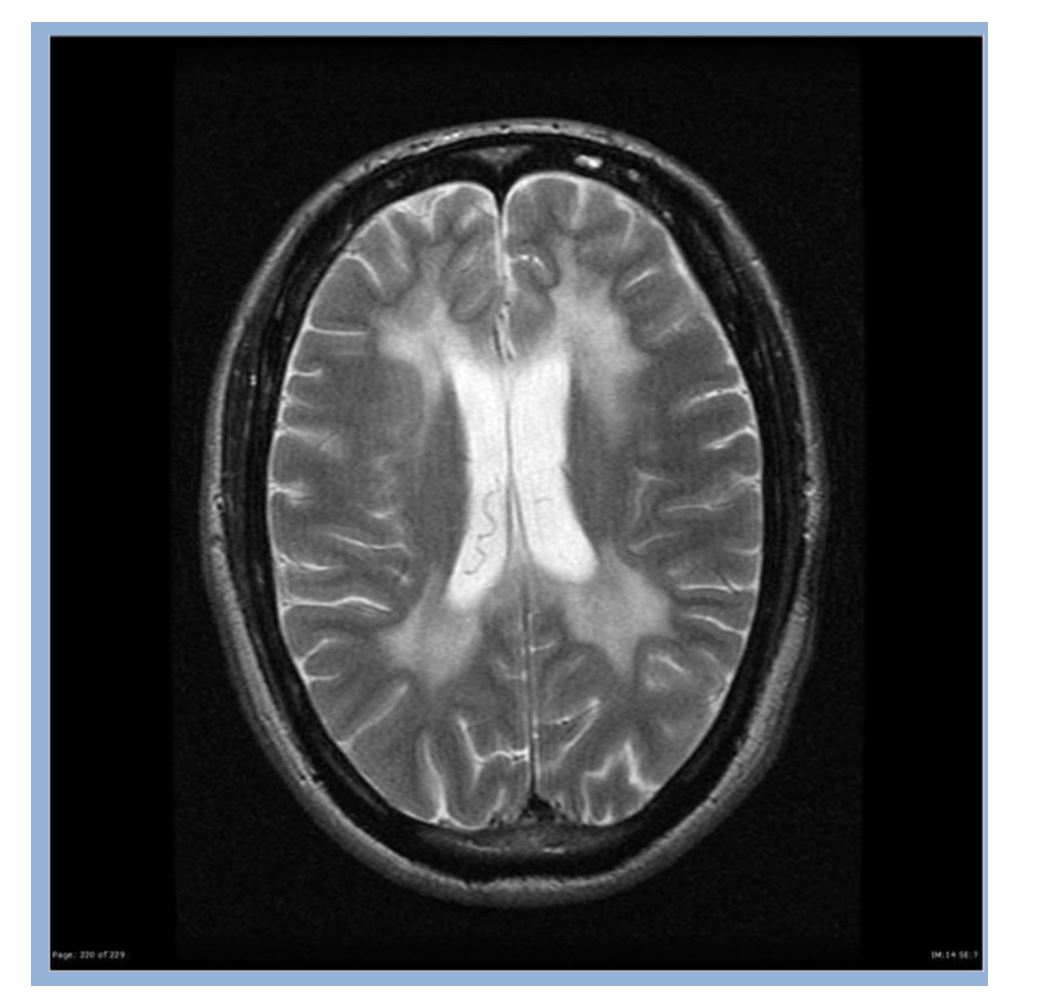

Figure 1